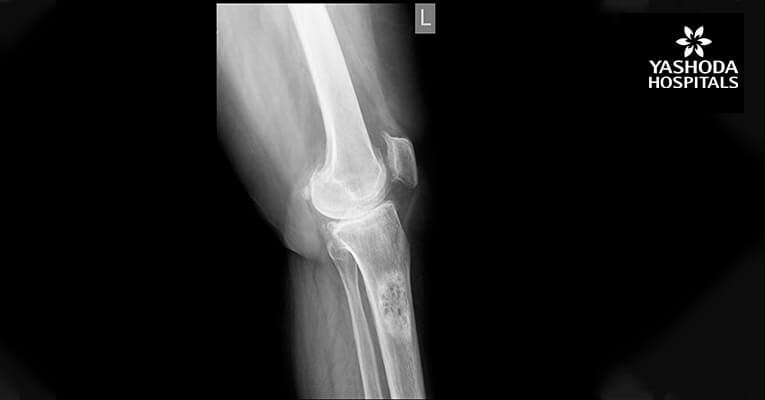

Continue reading...Distal Femoral Replacement for Severe Osteoarthritis Knee With Osteoporotic Distal Femoral Fracture

Background A 65-year old known rheumatoid female patient presented with severe pain in the left knee, difficulty in walking and performing daily activities. Clinical examination revealed severe osteoarthritis of the knees. She consulted several surgeons...